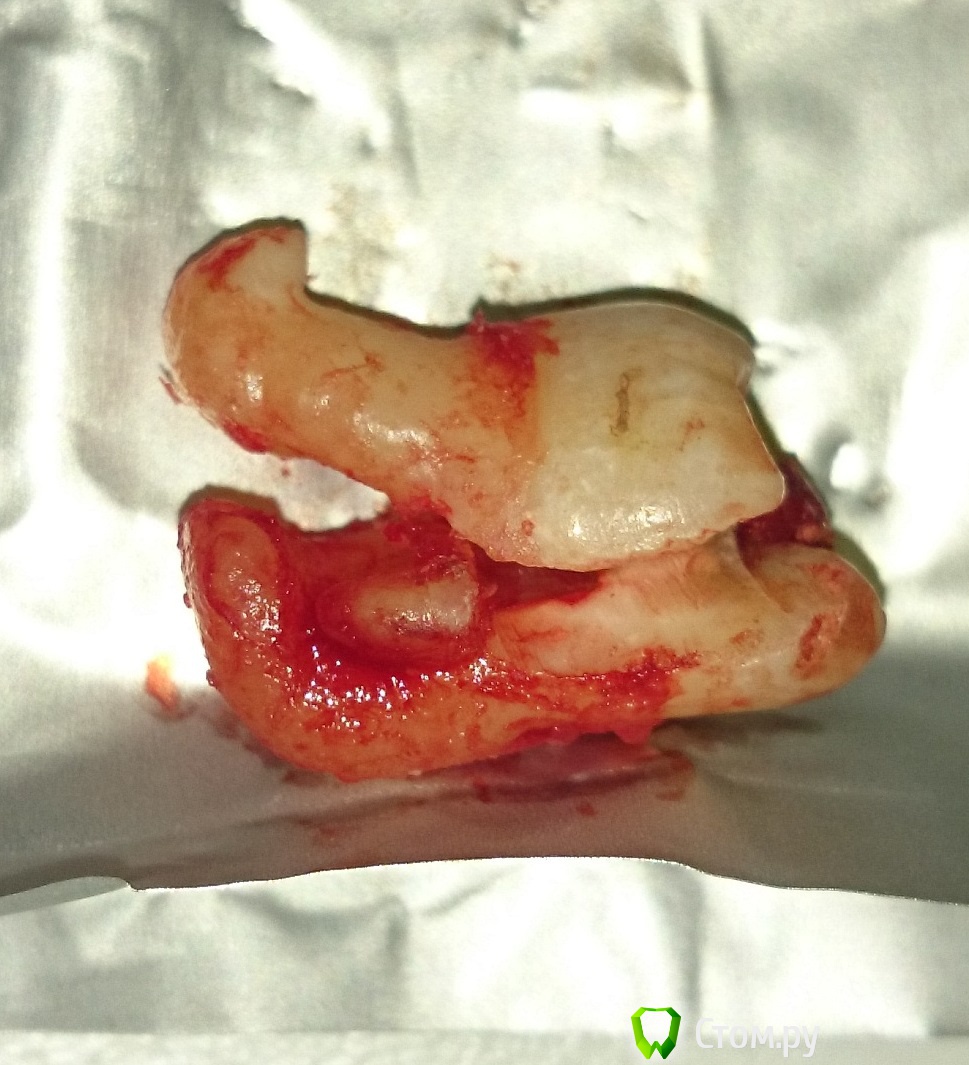

Larnary Опубликовано 21 июня, 2014 Поделиться Опубликовано 21 июня, 2014 (изменено) Вот такую восьмерочку только что удалил целиком.в самом конце выведения слегка треснула верхушка,но не сломалась Изменено 21 июня, 2014 пользователем Larnary 4 Ссылка на комментарий

Larnary Опубликовано 21 июня, 2014 Поделиться Опубликовано 21 июня, 2014 нет,зуб не болел.Травмировал сл.об.щеки .зуб был дистопированный в щеку. Ссылка на комментарий